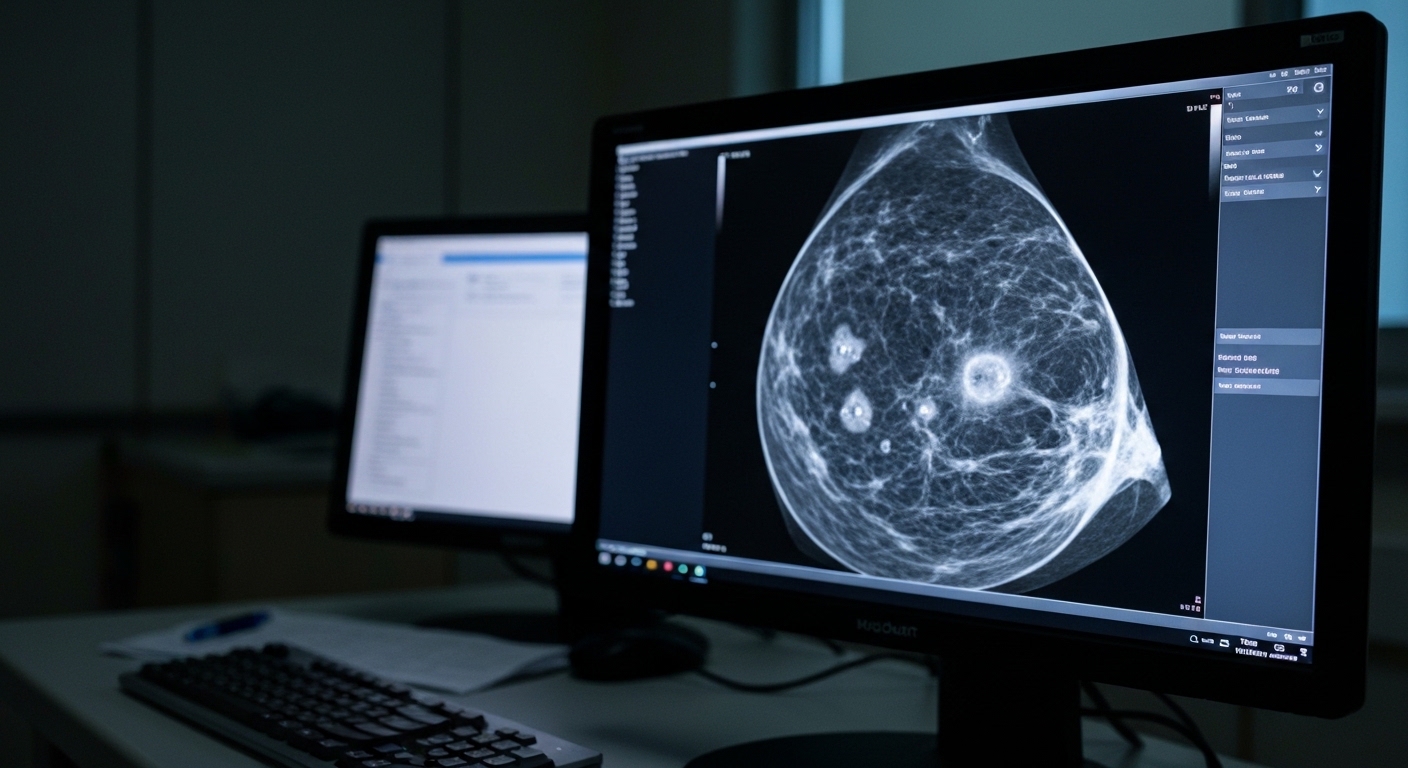

Breast cancer remains a leading cause of oncology-related mortality globally, necessitating precise risk stratification to optimize surgical and systemic interventions [1]. While traditional staging focuses on the size of the primary lesion and nodal involvement, the clinical significance of multifocality, defined as the presence of multiple synchronous tumor foci within the same breast, remains a subject of debate [2]. Current management strategies have evolved from mandatory mastectomy to include breast-conserving therapy for multifocal disease, provided that negative margins can be achieved [3, 4]. However, meta-analyses have produced conflicting data regarding whether these patients face a higher risk of systemic recurrence or breast cancer-specific death compared to those with unifocal tumors [5, 6]. A new national cohort study now provides evidence on how the number of invasive foci influences long-term survival outcomes.